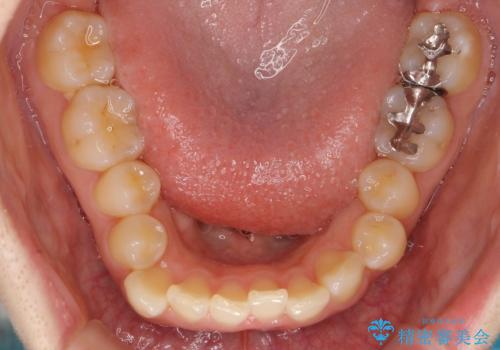

- 前歯のがたつきとガミースマイルの改善を希望して来院。

ガミーは非常に軽度でひどくはなかったのですが、改善を強く希望されていました。

上の前歯をひっぱりあげて目立たなくするために、上の前歯のワイヤー部分矯正を行い、ミニスクリューからわずかに引っ張り上げました。

また、右上の犬歯の反対咬合についてもワイヤー矯正で短期間で改善することができました。

前歯の過蓋咬合についても改善しています。